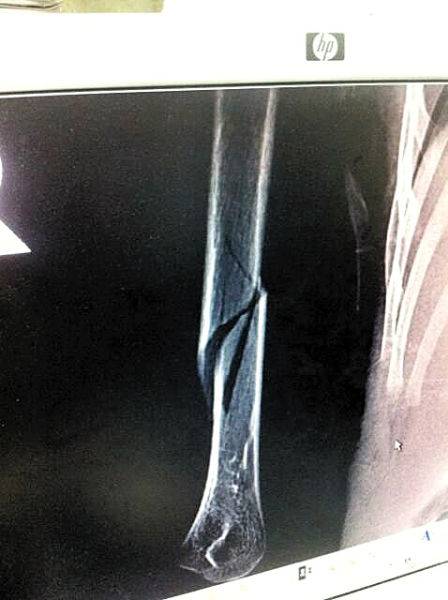

2014年8月19日广州, 4岁男孩被幼儿园老师带到了教室监控死角。2小时后,校医和园长发现他右手手臂肿痛、无力,被诊断为“右肱骨骨折”。涉事女老师解释称是失手拉伤,孩子称老师扭断其右手。